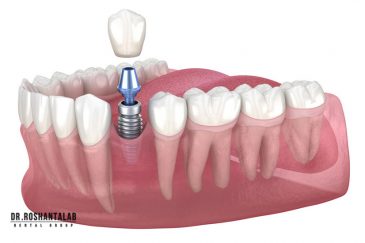

🔸 کاشت ایمپلنت دندان بدون درد

🔸کاشت ایمپلنت فلپ لس یا بدون جراحی و بدون بخیه زیر سه دقیقه

🔸 کاشت دندان یک روزه ( کشیدن و کاشت همزمان )

🔸 ایمپلنت دیجیتال و ساخت روکش دیجیتال

از عصب کشی و درمان ریشه دندان گرفته تا جراحی لثه و کشیدن دندان، تمامی مراحل توسط متخصص ترمیم دندان مدیریت میشود. ارائه باکیفیتترین خدمات ترمیم دندان برای سلامتی شماست.کاشت ایمپلنت فوری دندان

تجربه کاشت دندان دیجیتال و بدون درد در ۳ دقیقه! استفاده از برترین برندها زیر نظر جراح، با هزینه مناسب و خدمات کامل از کاشت دندان تا روکشارتودنسی دندان